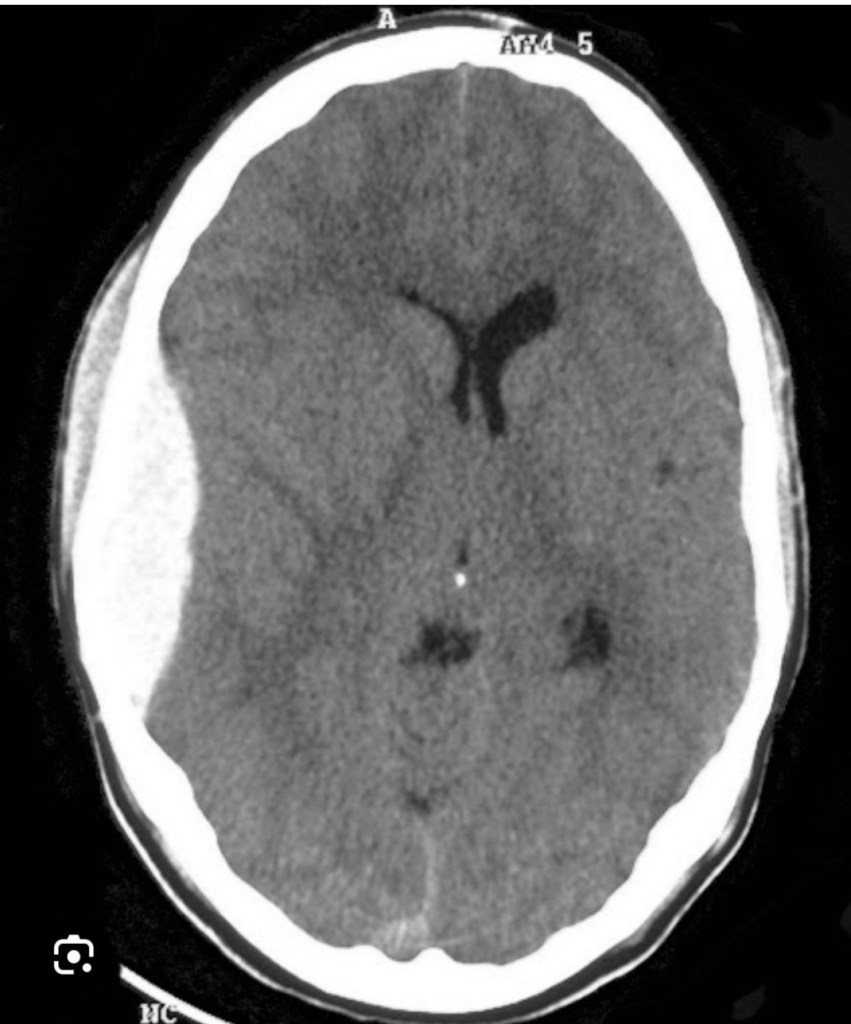

With the advent of CT Scan things have become easy, a convex opacity is seen in the scan and the degree of compression and deviation of the brain from the midline can be assessed.

Going by the history of lucid interval I could come to a diagnosis of extra dural haematoma but since we were in a remote area we didn’t have the facilities for a CT Scan to confirm my diagnosis.

I positioned him to left side with right side of the head up. I first made a vertical incision over the temporal region and made a burr hole, I got got clots from the burr hole, confirming my diagnosis.